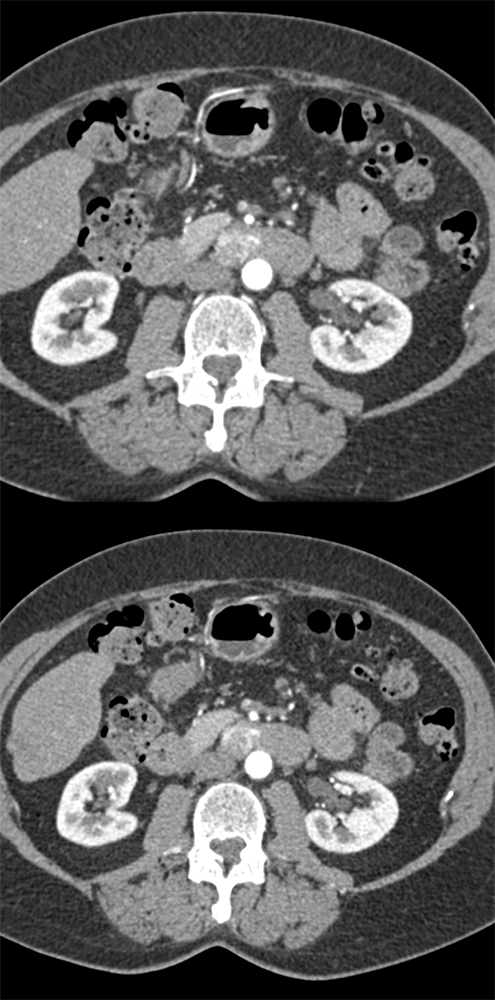

RCC Metastatic to Small Bowel ![]() |

![]() |